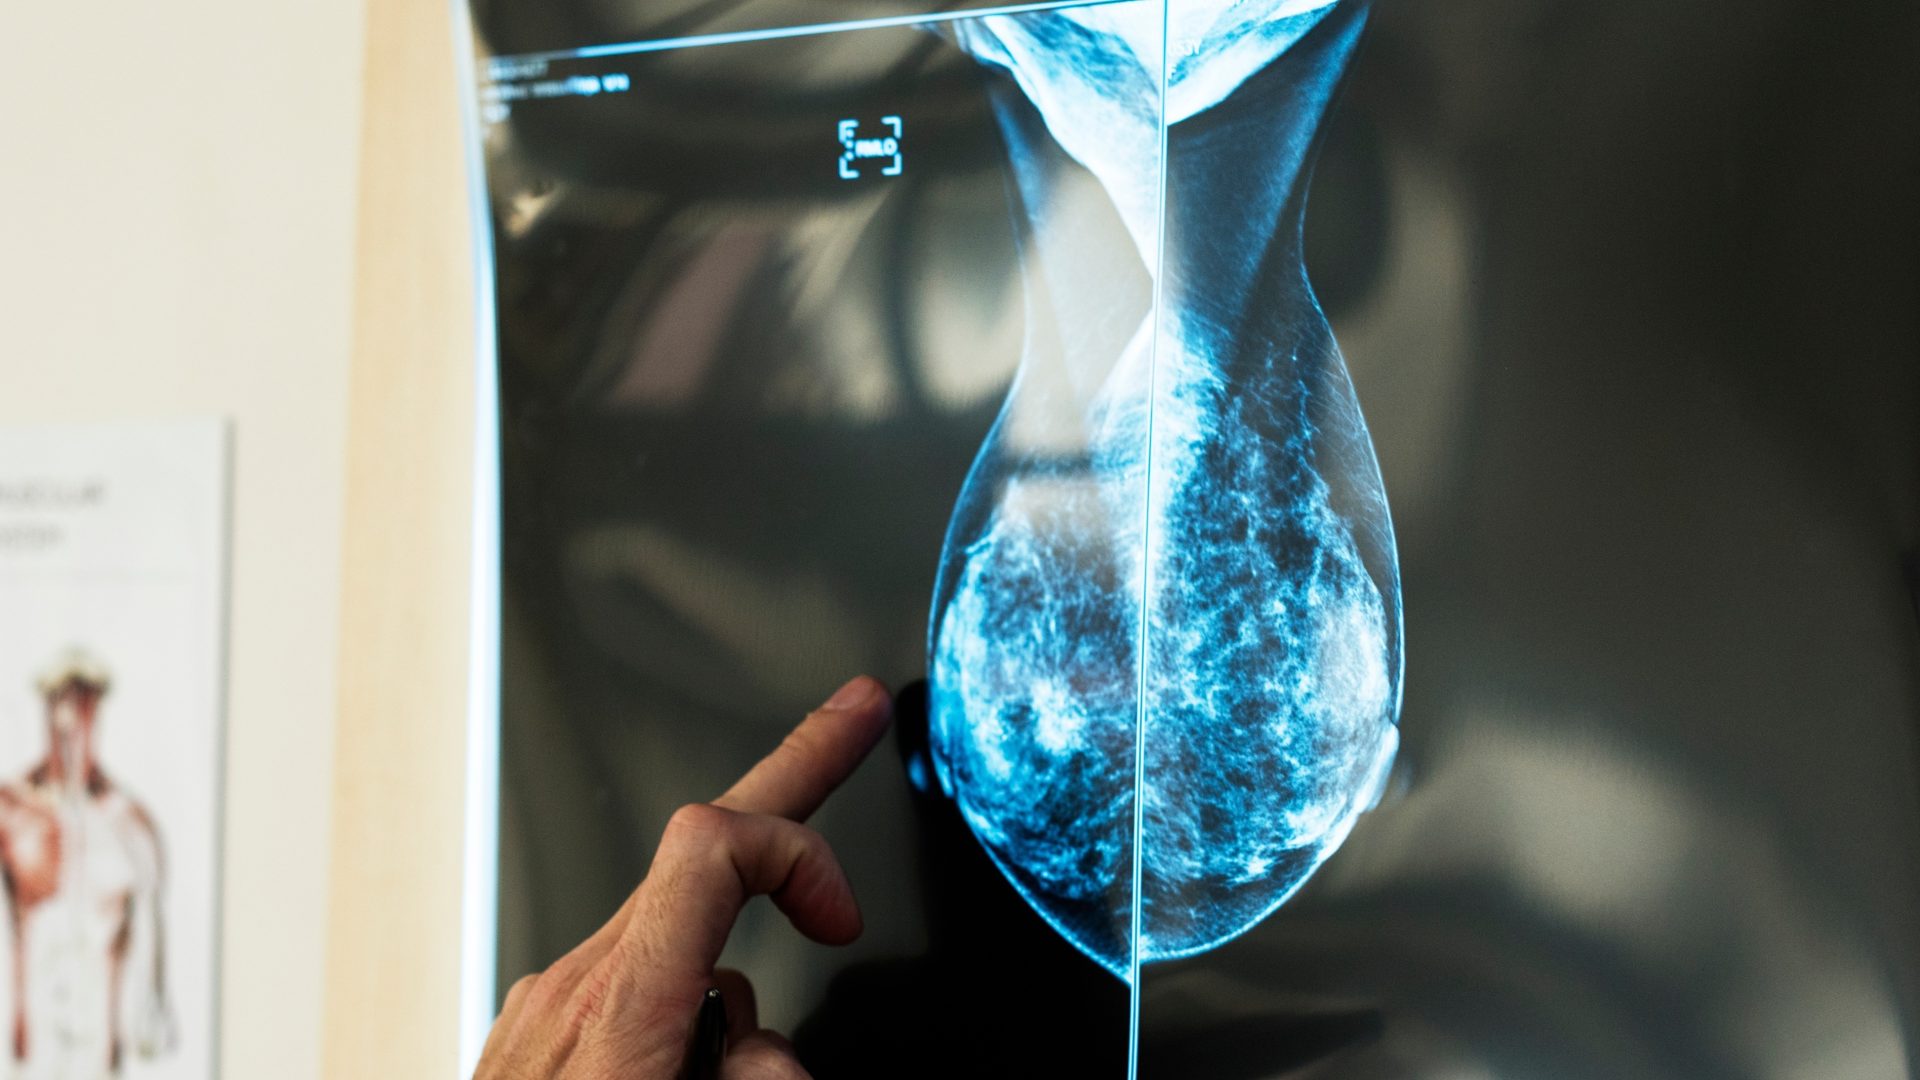

UCLA Fielding School’s Dr. Joann Elmore Co-Authors Research on AI and Breast Cancer Detection July 2, 2025